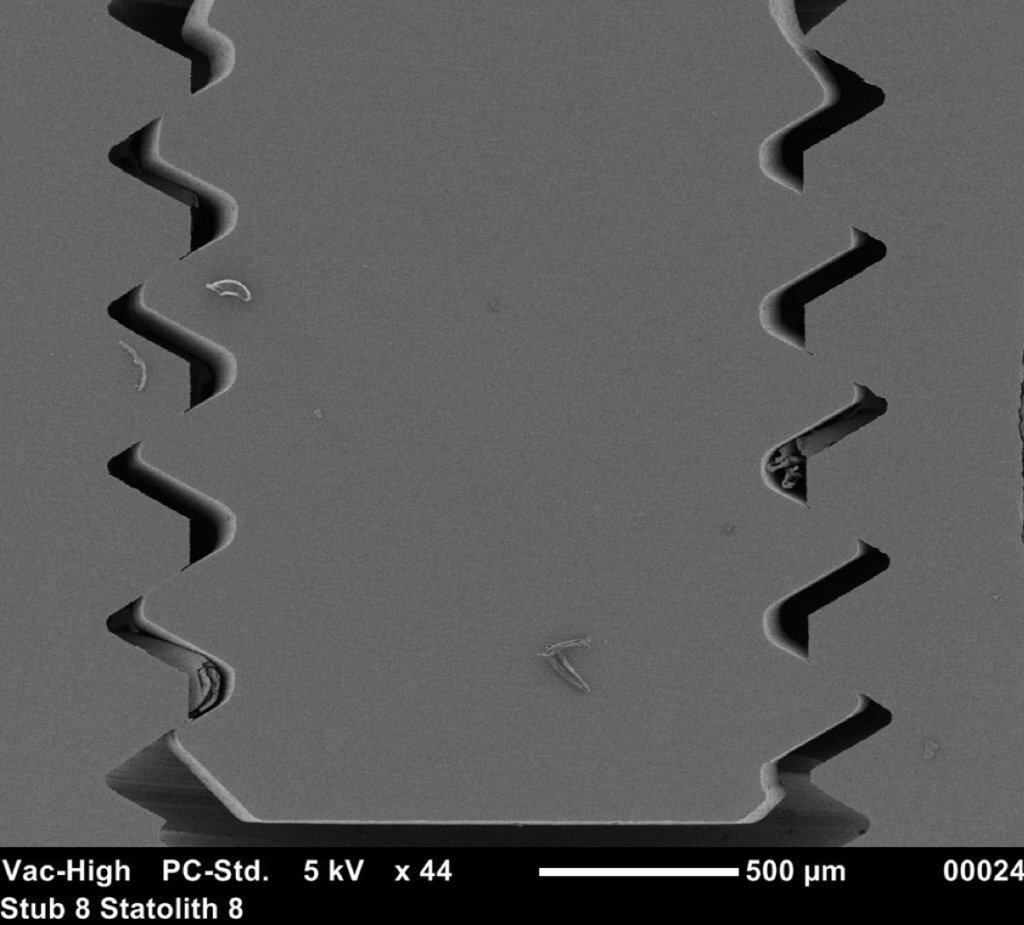

The “big deal” however was on the implant they used: It looked like Straumann, but it was not.

Not only it had very protruding threads, but there was an additional “pitch” at the top of each thread which would have probably made the traditional Straumann users of that time scream in disgust! So this implant never made it to humans, but remained in the notoriously small market of Beagle-dog implants. Nevertheless, this design was genius for the purpose of the experiment, as it created areas of compression (at the pitch of each thread) and areas of no contact, or empty chambers in the surface between two threads.

Right after implant placement, friction stability was achieved thanks to the pitches of the threads biting tight into the bone walls, while the non-contact areas filled with blood clot. The big news came however on the 4th day, when an interesting pattern of bone resorption occurred at the coronal side of the pitch! Why resorption? Obviously the compression of the bone there had killed a zone of bone about 50 μm, which was now being cleared away.

And why the top of the pitch and not the bottom? Well, this is actually screw mechanics. Regardless if you work with implants or with IKEA furniture, screws only apply force through the side of the thread which faces their side of insertion. A screw thread has actually only one working side. We learned this well when we were slicing implant-abutment junctions, only to see how little surface of the actual screw is engaging with the implant and always only the coronal part. (We learned a lot by looking at screws that time, but that would be probably a topic for another post). Common engineering never ceises to amaze!

To get the whole picture, we need to look closer at the other side of the coin and see what happens in the no-contact areas. There, at 1 week one could see another exciting development: contact osteogenesis! New mineralized bone was created on the surface of the implant in the empty chamber, where previously only blood clot existed. This was something hardly seen on the smooth surface implants, but was apparent in the SLA implants introducing another factor in the equation, the implant surface.

The collective message of these amazing experiments was the while bone is being cleared at the pitch of the thread, new bone is getting created on the implant surface at the no-contact areas! Surface is a significant factor here, with contact osteogenesis being well established at 2 weeks in humans with SLAactive implants, as documented by another great study by Lang et al (4). Lang as well, noted absence of new bone at the pitch of the thread after 1 week, but significant new bone in non-contact areas, where the “jumping” distance between the implant and the bone was short. Again, this message seen somewhat superficially, lead many to believe that the lower and fewer the implant threads, the better the implant would be, reinforcing the anecdotal concept of “aggressive” and “passive” implants. But as you can’t judge a book by its cover, you shouldn’t also judge an implant by its threads! The missing part here was that an implant with few and shallow threads will be unlikely to offer adequate primary stability!